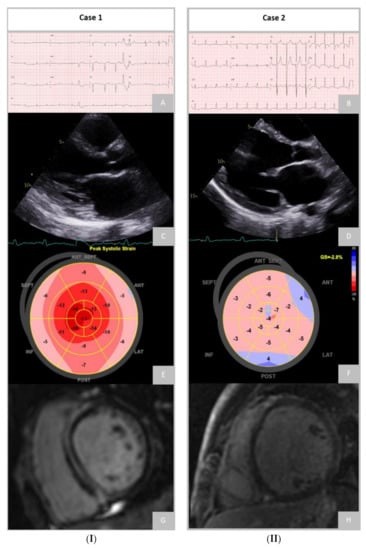

Differential Diagnosis of Dilated and Arrhythmogenic Cardiomyopathy